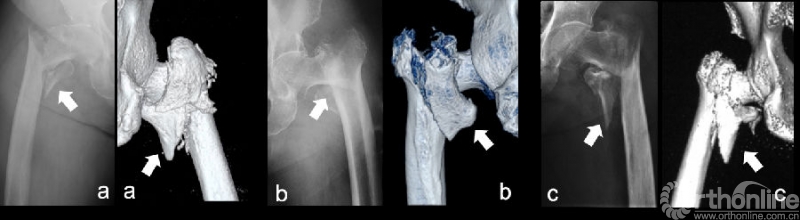

1. AO/OTA分型:记录术前骨折AO/OTA(Arbeitsgemeinschaft für Osteosynthesefragen/Orthopaedic Trauma Association,AO/OTA)分型,分型由2位有经验的骨科医师共同根据患者术前髋关节正侧位X光片重新评定得出(图1)。

图1: AO/OTA 31 A2型骨折分型

图3:82岁男性:(a)术前平片示右股骨粗隆间骨折,骨折AO/OTA分型为31 A2.1型,CT阅片明确内侧壁骨折为Ⅲ型。闭合复位后,(b)使用PFNA固定,未特意复位或固定内侧壁骨折块,术后可见内侧壁骨折块完全移位。术后1月常规复查时,平片(c)提示内侧壁骨折块位置无变化,仍移位明显。(d)术后3月时内固定切出。